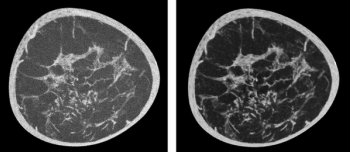

In a study of over 20,700 people, researchers found that artificial intelligence (AI) analysis of body composition measurements via lung cancer screening computed tomography (CT) exams improves the prediction of mortality risks for lung cancer, cardiovascular disease, and all-cause mortality.